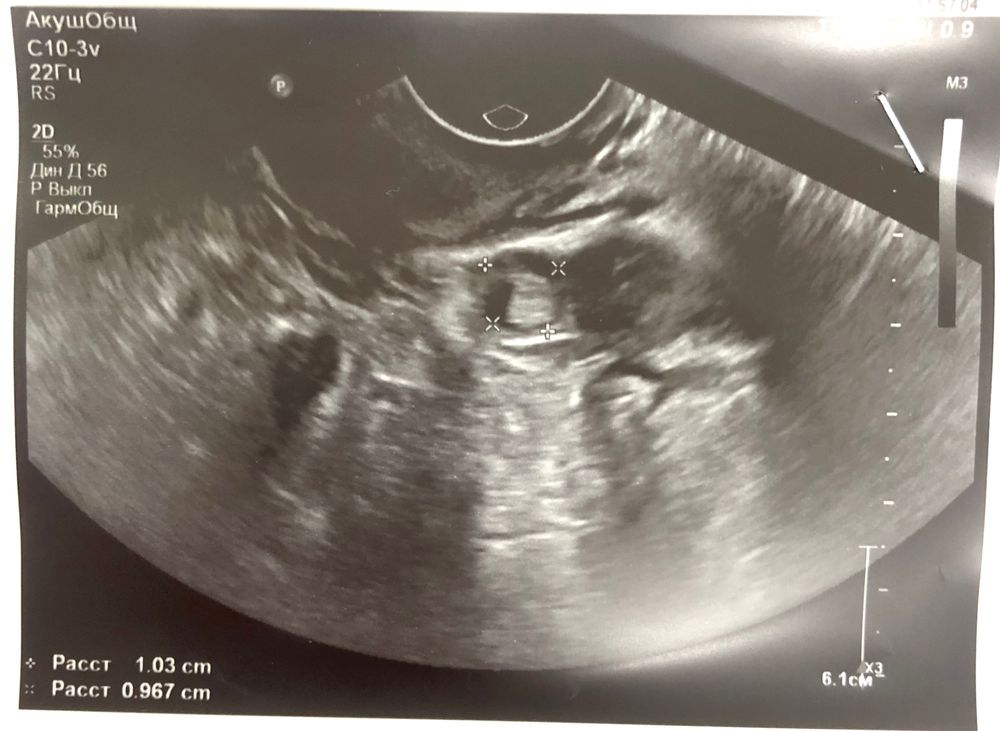

Не плодное яйцо это,а что-то другое вам там в трубе нашли с хгч 363 никакого плодного ещё не видно нигде,плодное 3 мм можно разглядеть при хгч минимум 750 и то не всегда,а у вас прям пя нашли свд 10 мм при хгч 300? Не сходиться чтоб найти такого размера пя хгч от 10 тысяч должен быть,от уровня хгч зависит размер плодного яйца

Как то не вяжется ПЯ 10 мм и хгч 363 ,переделайте УЗИ если есть такая возможность.И главное верьте в чудо ,хотя это конечно очень сложно .